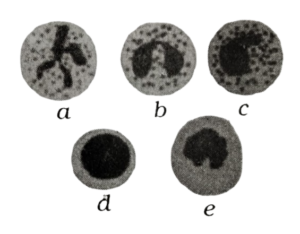

Solution:neutrophil, b - eosinophil c- basophil, d - lymphocyte -monocyteWhite blood cells, also known as leukocytes, are immune cells that circulate in the blood and lymphatic system. The five types of white blood cells shown in the picture are as follows:

• Neutrophils - main action against bacterial and fungal infections.

• Eosinophils - main action against parasitic infections.

• Basophils - responsible for responses to allergens.

• Lymphocytes - main action against viral infections.

• Monocytes - main action against bacterial infections.